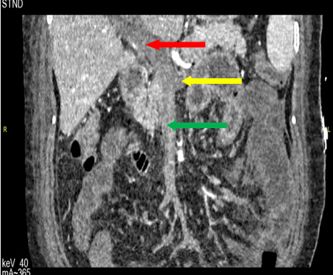

我们在患者入院第10天时试验性经鼻胃管注入葡萄糖溶液,患者没有出现明显不适,但随着进食量的增加,患者出现轻微腹痛症状,复查门静脉系统CTA并对比老片提示脾静脉部分再通(见图D)。

家属携带我们的检查资料和患者当前的病情介绍咨询了省会医院的专家,最终转去省会的医院继续治疗。后续追踪患者病情,患者于省会某权威医院行肠系膜上动脉溶栓治疗,但溶栓后血栓未能再通,后行剖腹探查行坏死肠道切除术,目前患者处于康复状态。

图D:门静脉系统CTA(2018.04.24):脾静脉可见部分造影剂充盈(黄色箭头代表脾静脉)